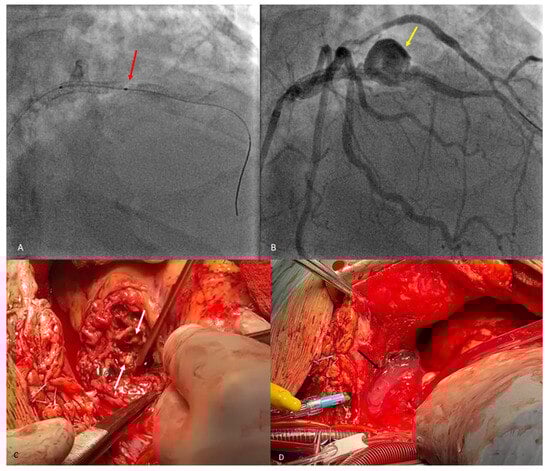

Figure 3. A classic coronary angiography was performed next, where a type IV distal stent fracture involving the proximal LAD stent with dehiscence and slight migration ((A), red arrow) associated with a coronary pseudoaneurysm ((B), yellow arrow) were observed. An attempt was made to install a pharmacologically active post-dilation balloon stent in order to treat the pseudoaneurysm, but without success, which is why the patient was transferred to the cardiovascular surgery ward. The surgical procedure was performed under general anesthesia with orotracheal intubation and extracorporeal circulation, and the final diagnosis was a stent fracture associated with pseudoaneurysm formation and infected pericardial hematoma. Intraoperative view of the complete stent fracture and separation ((C), white arrows). Infected pericardial hematoma ((D), black arrow). The case is atypical, as the stent fracture was type IV (complete transverse fracture of the stent with separation into two fragments and displacement) and occurred at the level of the anterior descending artery. The most common stent fractures reported in the literature involve the right coronary artery, with a more tortuous course, and type III and IV fractures have the lowest incidences [4]. Coronary pseudoaneurysms following stenting are rare complications with an incidence of 0.3–6% and usually arise approximately 6–9 months after the intervention, but cases have been reported earlier than 2 months after the procedure [5]. Unlike similar reports in the literature [6], the attempt to implant a new drug-eluting stent in our patient failed. Finally, surgical revascularization proved to be the appropriate treatment strategy. After removing the pseudoaneurysm and performing an aorto-coronary bypass, the patient showed a favorable recovery and was discharged in a stable condition. Invasive coronary angiography is considered the gold standard for diagnosing intra-stent restenosis, although the invasive nature of the procedure comes with associated risks of mortality and morbidity. Computed tomography angiography (CTA) is a non-invasive imaging technique highly beneficial for follow-up consultations. Coronary artery intrastent restenosis detection has been determined to have high specificity when at least a 64-multislice CT technique is used. CTA can and should also be used when varying symptoms appear after an interventional coronary procedure [7].